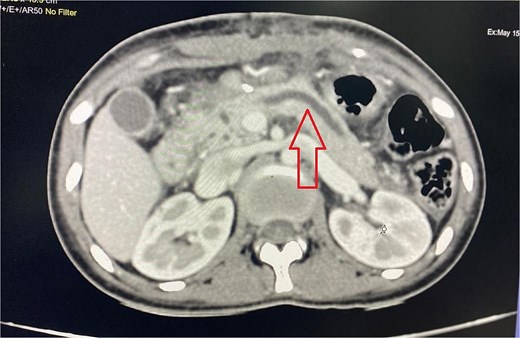

Imaging from an ultrasound indicated the main pancreatic duct was dilated to 4 mm, and a computed tomography (CT) scan confirmed dilated pancreatic duct with a Modified CT Severity Index of 4 (Fig. 1). A magnetic resonance cholangiopancreatography (MRCP) revealed a Type 3B biliary duct variation and ansa pancreatica, a looping duct connecting the main and accessory ducts draining via the minor papilla (Fig. 2).